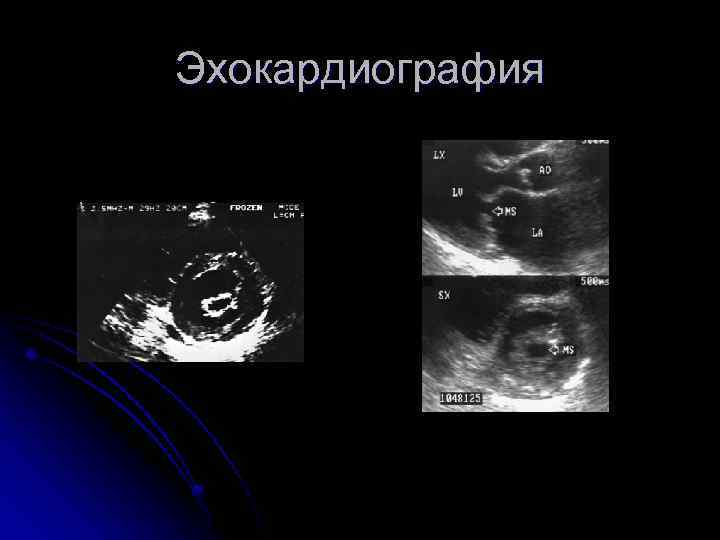

3. Эхокардиография Уплотнение, кальциноз МК l “Парусение” передней створки МК в диастолу l Площадь МО PG Легкий МС >1, 5 см² <5 мм рт. ст. Умереный МС 1 -1, 5 см² 5 -10 Тяжелый <1 см² >10 l Оценка перегрузки камер сердца Дилатация ЛП (N 40 мм) Дилатация ПЖ l Оценка ЛГ (N СДЛА 25 -30 мм рт. ст. ) l Наличие тромбов в ЛП l Относительная недостаточность клапана ЛА, ТК (регургитация на этих клапанах) l

Эхокардиография